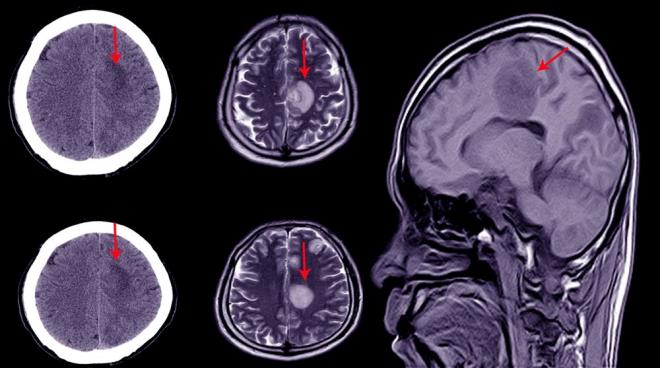

KAFATASI SIVI İLE DOLU 2007 yılında The Lancet dergisinde yayımlanan bu hikaye, bilim dünyasında büyük bir yankı uyandırdı. 44 yaşındaki adam bacağında güçsüzlük hissi yaşaması üzerine doktora gitti. Yapılan muayenede, beyninin büyük bir kısmının kayıp olduğu ve kafatasının sıvı ile dolu olduğu belirlendi. Bu durum hidrosefali olarak biliniyor.

NORMAL BİR YAŞAM SÜRÜYOR Bilişsel psikolog Axel Cleeremans, adamın normal bir yaşam sürdüğünü, bir ailesi ve işi bulunduğunu belirtti. Adamın IQ testi 84 olarak ölçüldü. Normal aralığın biraz altında ancak bu durum adamın yaşamını etkilemedi.

Çocukken bir stentle tedavi edilen adamın, stent çıkarıldıktan sonra beyninin büyük kısmı aşınmıştı. Beyin taramalarında, beyin dokusunun büyük kısmının sıvı ile dolduğu ve tahrip olduğu gözlemlendi.